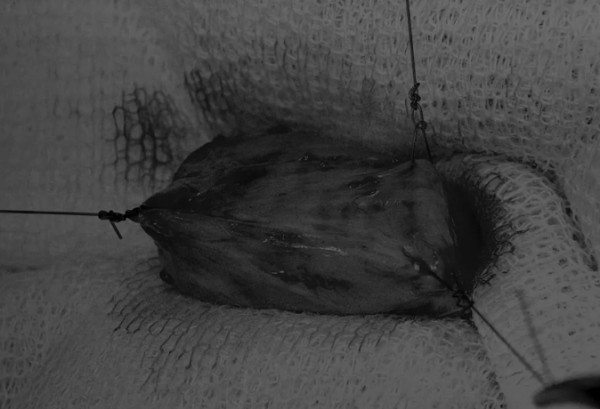

在中线开腹手术后,确定膀胱,将其取出并隔离(图1)。为了使膀胱持续暴露,可在膀胱中线两侧各放置一根固定缝线(图2)。

图1 将膀胱从腹腔中取出,用无菌外科敷料隔离。为了防止膀胱滑入腹部,可在膀胱顶部放置一根固定缝线,由助手通过止血钳夹住固定缝线做持续牵引